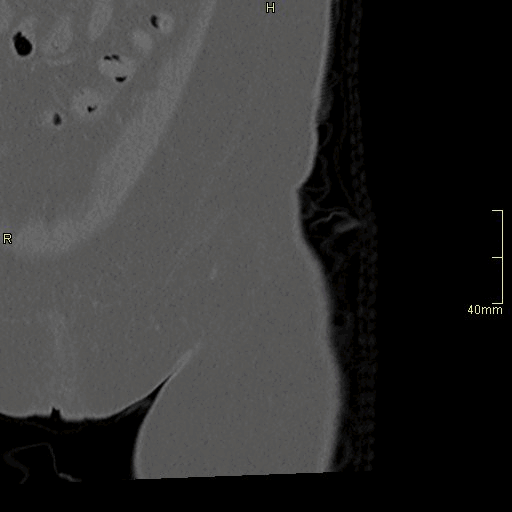

CT Hip Contrast- Bone window (axial)

CT Hip Contrast- Bone window (coronal)

CT Hip Contrast- Bone window (sagittal)

CT Hip Non Contrast- Bone window (axial)

CT Hip Non Contrast- Bone window (coronal)

CT Hip Non Contrast- Bone window (sagittal)